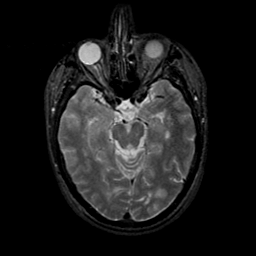

MR Study #9, April 14, 1991 -- Slice #19